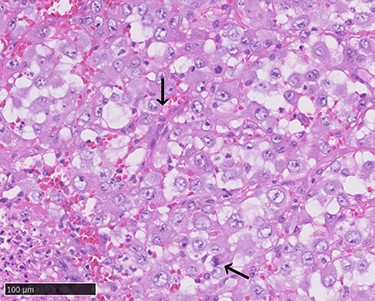

Arteriovenous malformation (AVM) in the right upper limb reaches to the shoulder.

A 70-year-old Japanese woman was referred to our department. Her medical history indicated surgery, radiation therapy and intravascular treatment for AVM in her right upper limb since she was 17 years old (Fig. 1). One month before initial presentation, she noticed frequent haemorrhagic masses in her oral cavity. She complained of general malaise and loss of appetite. The masses bled readily upon scraping the hard palate (Fig. 2A). Similar masses were found on her left lower gingiva (Fig. 2B). Routine blood tests revealed normocytic normochromic anaemia of 4.6 g/dl, while no platelet or coagulation abnormalities were found. Open incisional biopsy under general anaesthesia was performed after conservative management, including blood transfusion, nutrition and oral care. The masses had grown rapidly and covered the hard palate and had spread to the upper gingiva, maxillary bone and maxillary sinus (Fig. 2C and D). The specimen consisted of bloody, dark-red and partially sponge-like lesions. Histologically, necrosis and haemorrhage were evident. In areas where viable cells were present, atypical, vascular endothelial cells with pleomorphic nuclei formed a solid lesion or a network to form a narrow lumen filled with blood cells (Fig. 3). Immunohistochemical staining was positive for CD31, CK (AE1 + 3), ERG, D2–40 and CK (CAM 5.2) and negative for CD34, FactorVIII, αSMA, MyoD1, Desmin, Myogenin, S100, HMB45, MelanA, CK (5/6), p63, p40 and EMA. MIB-1 staining showed a proliferation index as high as 50%. These pathohistological findings revealed the tumour as AS (FNCLCC Histological Grade 3).